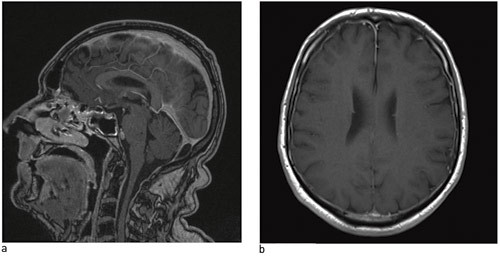

In cases of low-pressure headache, including post-dural puncture headache, MRI of the head tends to show diffuse pachymeningeal enhancement due to the contrast medium (Fig. 2) and reduced ventricle size; the cerebellar tonsils may extend down into the foramen magnum and basal cisterns may be flattened or eliminated, or the hypophysis may be enlarged (11). In the event of doubt, CT myelography, cisternography or spinal MR with thin sections may reveal where the cerebrospinal fluid leak is located (38).